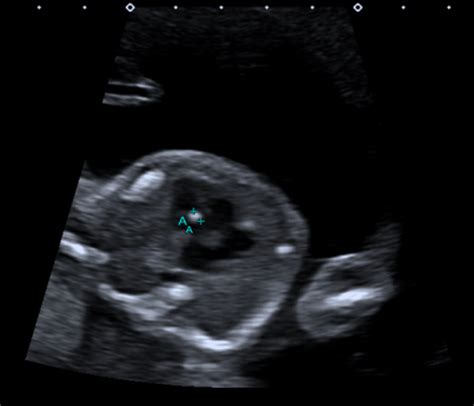

The 20-week anatomy scan is a routine ultrasound offered by the NHS to pregnant women, typically performed between 18 and 21 weeks of gestation. Its primary goal is to assess the physical development of the fetus and identify any major congenital anomalies. During the scan, a trained sonographer will meticulously examine various organs and body parts, including the brain, heart, spine, kidneys, and limbs. They’ll also check the position of the placenta and measure the amniotic fluid levels. This comprehensive evaluation aims to provide parents with as much information as possible about their baby’s health, allowing for timely intervention and informed decision-making if necessary.

The importance of the 20-week scan cannot be overstated. It serves as a crucial screening tool, detecting a wide range of conditions, from structural abnormalities like spina bifida and cleft palate to heart defects and kidney problems. Early detection allows for better management of these conditions, potentially improving outcomes for the baby after birth. In some cases, the scan may reveal a minor issue that requires no intervention at all, providing reassurance to expectant parents. However, if a more serious problem is suspected, the scan results will prompt further investigations and consultations with specialists. Remember, the 20-week scan is just one piece of the puzzle. It’s designed to identify potential risks, but it’s not always definitive. Further tests and expert opinions are often needed to confirm a diagnosis and determine the best course of action. So, try to stay calm and gather all the necessary information before jumping to conclusions.